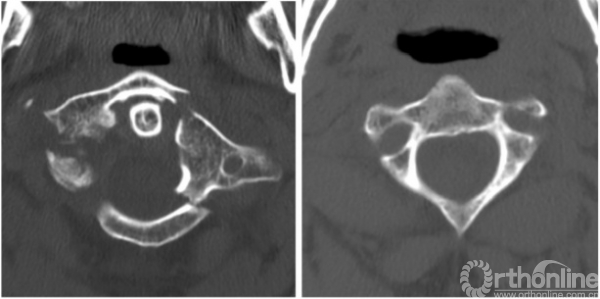

2014年5月,一名50岁男子因车祸入住我院。颈椎计算机断层扫描(CT)显示寰椎前弓及后弓多处骨折,侧块后1/3处分离(图1,左)。患者出现严重的颈部疼痛,当移动头部时疼痛剧烈,除此之外,无神经系统症状。同时合并有脑外伤、左侧额、颞部线性骨折以及头部软组织损伤,使我们在很长一段时间内无法使用Halo架固定。

最初,我们计划使用Harms技术进行C1-C2固定,用螺钉将寰椎碎裂的侧块融合。然而,病人的解剖特征使得这一方法不可行:其椎动脉位于C2椎体右侧,使右侧无法进行关节融合术。而C2右椎弓根、峡部、弧形部体积小,也使C1-C2的后路螺钉固定技术无法实施(图1,右侧)。由于这些限制,我们采用了前路经寰枢关节交叉螺钉固定技术(图2)和后路的Magerl技术[7]。

图1案例1:颈椎术前CT扫描,左C1椎体多节段骨折,C2椎弓根、关节旁变薄,C2侧块的前缘两侧变薄;CT,计算机断层扫描

A 50-year-old man was admitted to our department in May 2014 after a car accident. Cervical spine computed tomography (CT) scans revealed multiple fractures in the anterior and posterior arcs of the atlas and abruption of the posterior third of its lateral mass (Fig.1,left). Clinical symptoms included severe cervical pain that increased dramatically when the patient moved his head; otherwise, he was neurologically intact. The concomitant traumatic brain injury, linear fracture of the left frontal and temporal bones, and soft tissue wound on the head prevented us from using the Halo device for an extended period of time. Initially, we planned to perform C1-C2 fixation using the Harms technique and fusion of the shattered lateral mass of the atlas with a screw. However, the patient’s anatomical characteristics prevented this. The location of the vertebral artery on the right side of the C2 vertebra made it impossible to perform transarticular fusion on that side. The small size of the C2 right pedicle, pars interarticularis, and arc also made it impossible to use the posterior screw fixation technique of C1–C2 on the right side (Fig.1,right). Due to these limitations, the combined anteroposterior atlantoaxial fixation technique with contralateral screw insertion (Fig.2) and Magerl trajectory[7]was performed.

Fig. 1 Case 1: pre-operative CT scan of the cervical spine. Left multisplintered fracture of the C1 vertebra. Right thinning pedicle, arc, and parsarticularis of the C2 vertebra as well as bilateral thinning of the anterior lip of the C2 lateral mass. CT computed tomography